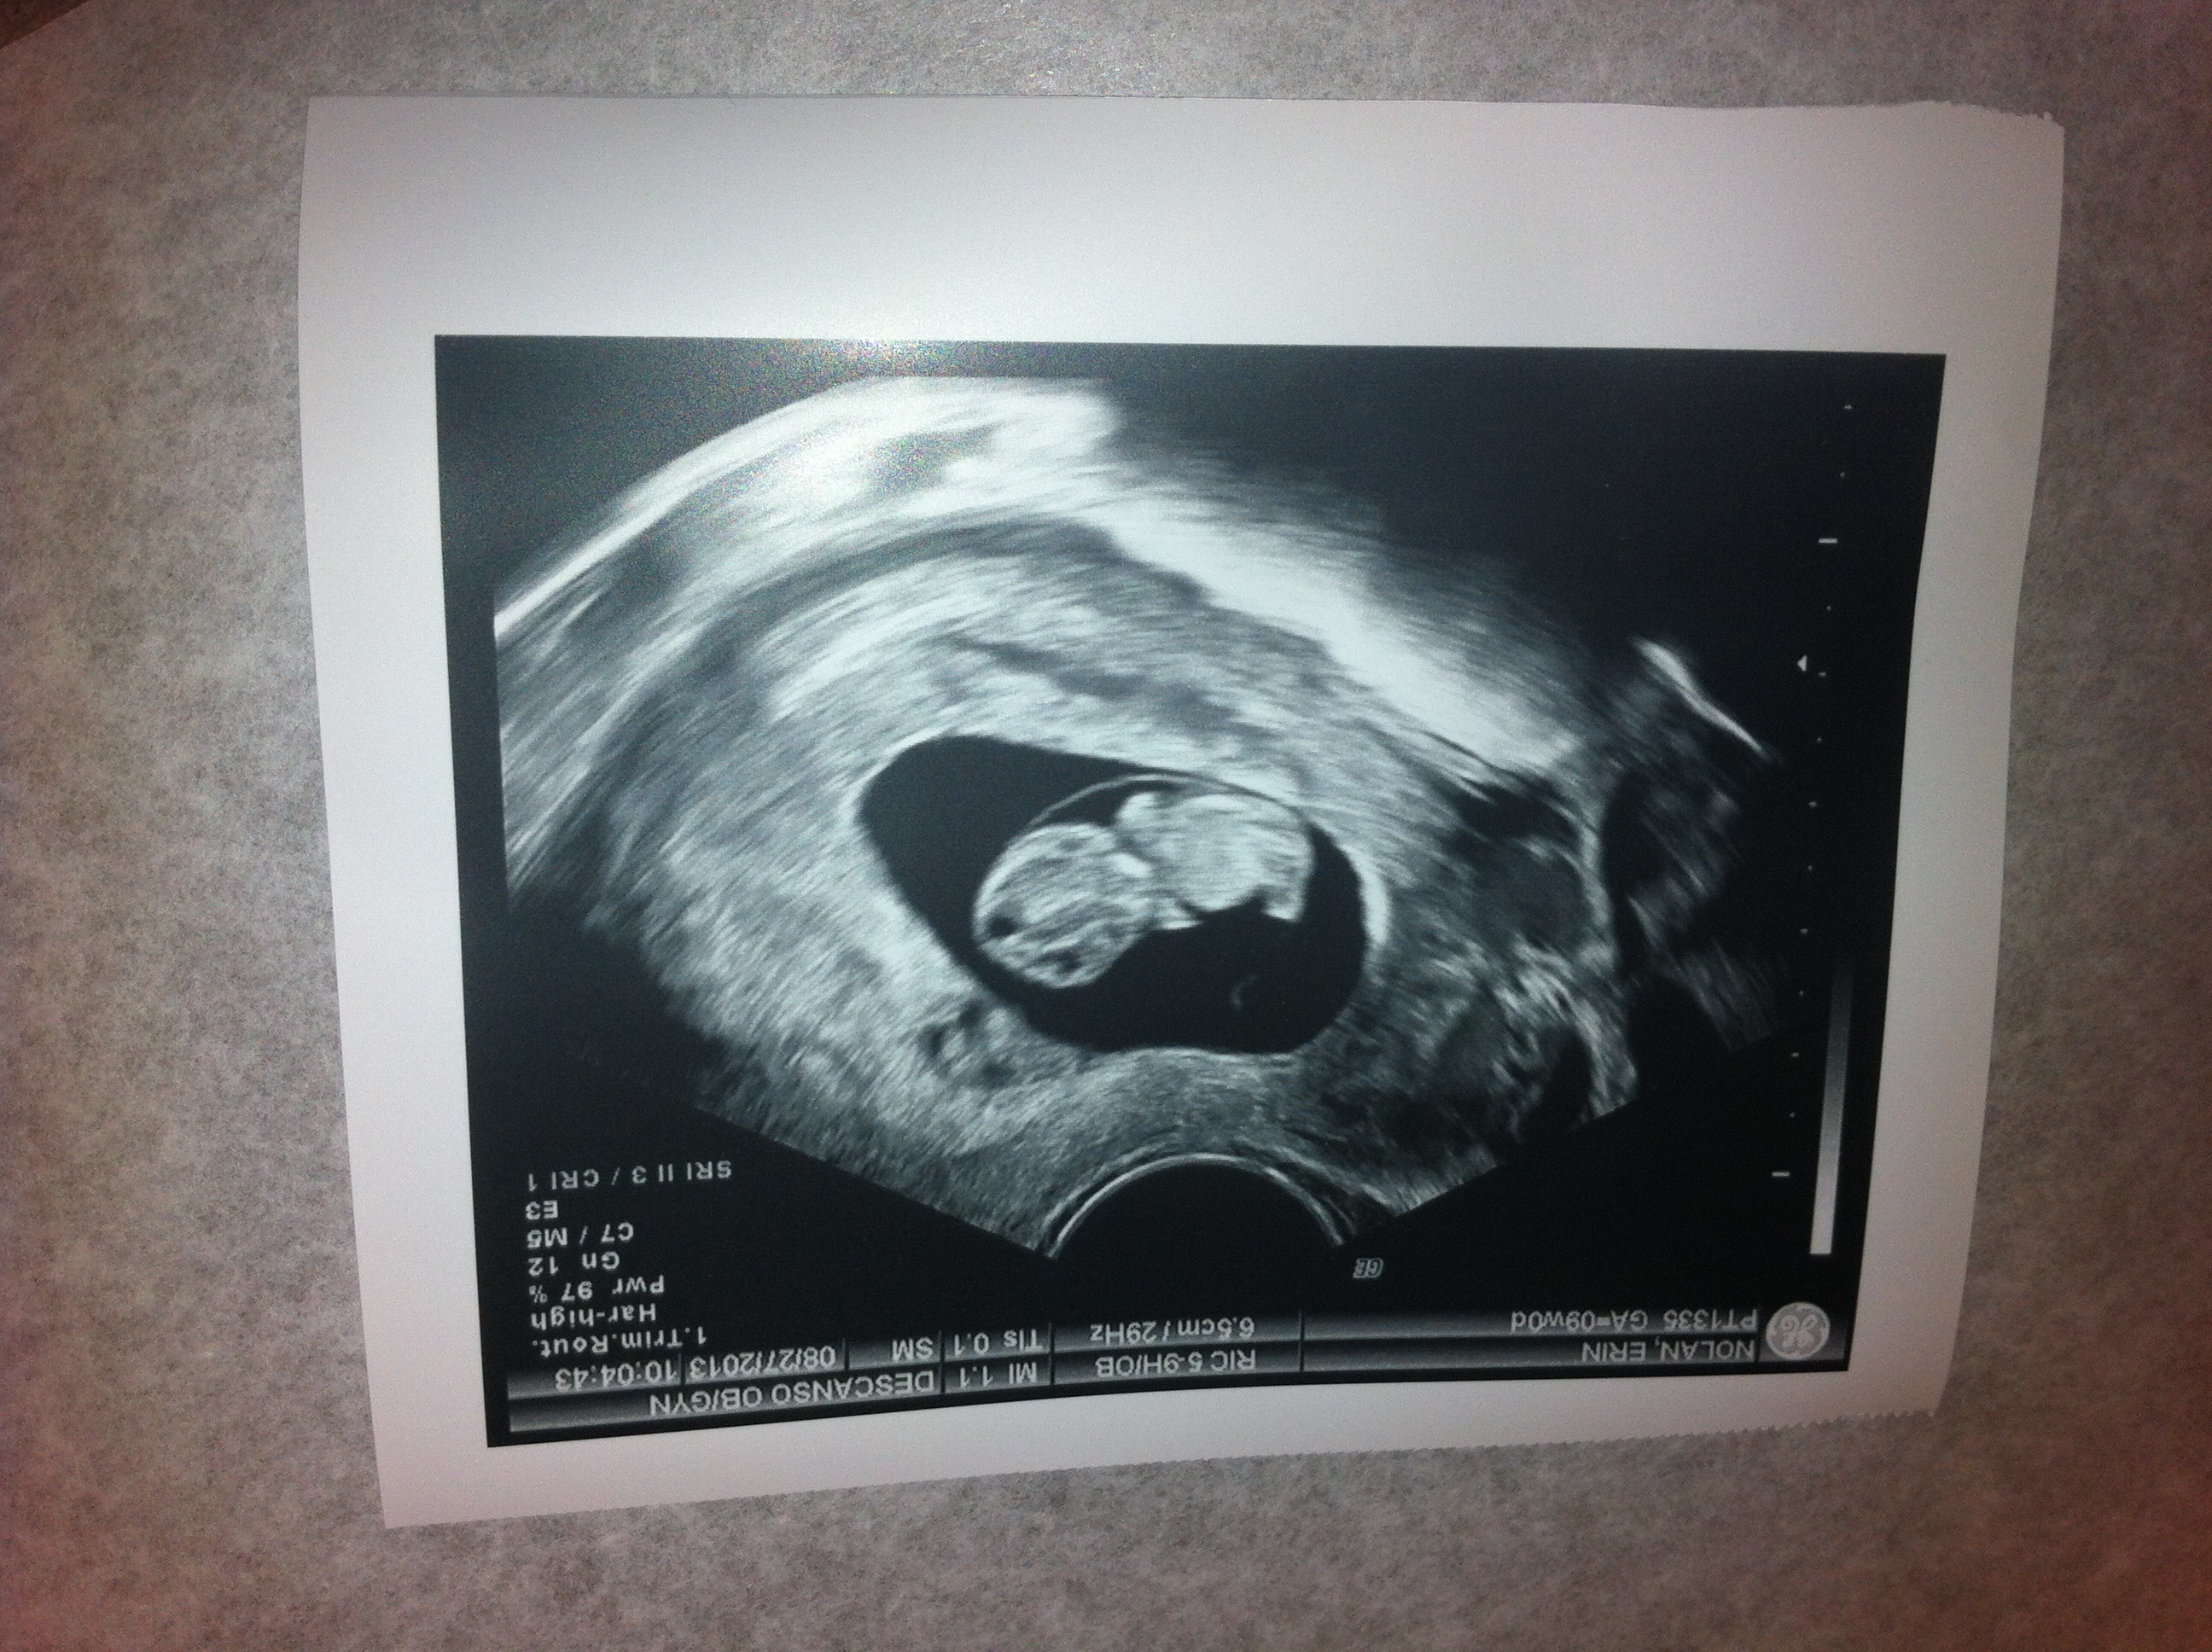

My little one is happy and healthy! He/she has the cutest little belly already, too. Baby was moving up a storm during the ultrasound, kicking and waving. I think this pregnancy has finally hit home for me. This is really happening. Blissfully happy right now. Not sure why my photo is loading upside down... iPhone vs The Bump issues, I guess.